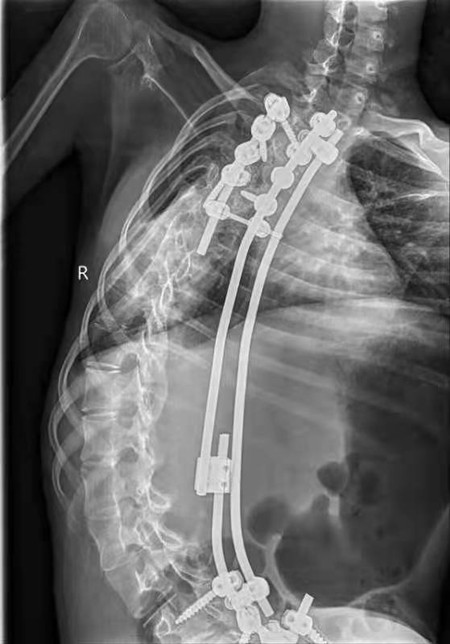

自2019年2月SMA基因修饰治疗药物上市以来,黄宝宝的妈妈就四处筹钱为患儿治疗。2021年9月份,妈妈来到交大二附院儿科为患儿进行治疗。黄宝宝刚来到医院,就受到了儿科神经病区的重视,在黄绍平教授和杨琳教授带领下,由儿童神经专业团队为黄宝宝进行了专业的评估和相关的检查。经过评估后发现黄宝宝的运动功能严重落后,下肢不能做任何平面的活动,上肢只能进行手指及肘关节的轻微活动,头部的活动也严重受限,各项神经运动功能评分均很低。患儿在3个月前在其他医院进行了脊柱侧弯的矫正手术,手术后患儿的脊柱侧弯虽减轻,但仍严重,而且脊柱固定,不能活动。因为SMA基因修饰药物是需要进行腰椎穿刺术鞘注给药的,为确保患儿能顺利用上药物,黄绍平教授、杨琳教授组织了骨科、影像科及B超室多学科联合会诊。骨科李浩鹏教授看过患儿后认为她脊柱侧弯严重,盲穿成功的可能性不大,在B超或CT引导下进行穿刺成功概率较大,因为CT引导下有辐射,患儿需要反复穿刺鞘注,所以首选B超引导下进行穿刺。B超室何鑫医生为患儿进行了B超引导下的穿刺点定位,认为B超引导下进行腰椎穿刺定位是可行的。CT室的刘乐医生认为,如果B超引导下不能穿刺成功,可以在CT引导下再进行尝试。经过前期充分的准备。定于9月18日早8点在B超室进行穿刺。

9月18日早8点,黄宝宝在妈妈、李丹副主任医师、王雪莹主治医师和高丹住院医师的陪同下来到B超室。B超室何鑫医生为黄宝宝再次进行穿刺前的定位,经过常规的消毒、铺巾、局部麻醉等操作后,在B超引导下进行了穿刺。因为患儿脊柱侧弯并进行了脊柱融合固定手术,为了寻找最合适的进针角度,何鑫医生只能采取蹲位,凭着他高超的穿刺技术,很快腰椎穿刺针里流出了清凉的脑脊液。为了确保鞘注治疗顺利,何鑫医师一直保持蹲位的姿势,在李丹副主任医师的配合下,经过大约40分钟的努力,患儿终于成功、安全地进行了鞘注治疗,拔出穿刺针,何鑫医生起来时,由于长时间保持蹲位,不由得打了个趔趄,向后晃了几步,在场的医护赶紧扶住他,此时大家全都松了一口气。术后患儿安返病房,各项生命体征平稳。